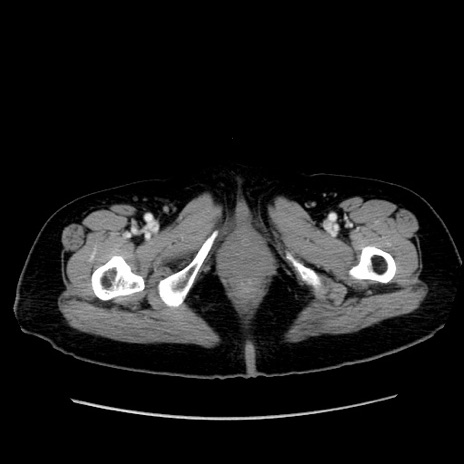

症例19(横断像)

【症例】80歳代女性

【主訴】下腹部痛

【現病歴】約8時間前より下腹部痛の出現あり、救急外来受診。

【既往歴】両側付属器切除

【身体所見】意識清明、下腹部正中に手術痕あり、その部位に一致して圧痛と反跳痛あり。腸蠕動音は亢進。

【データ】WBC 9300、CRP 0.15